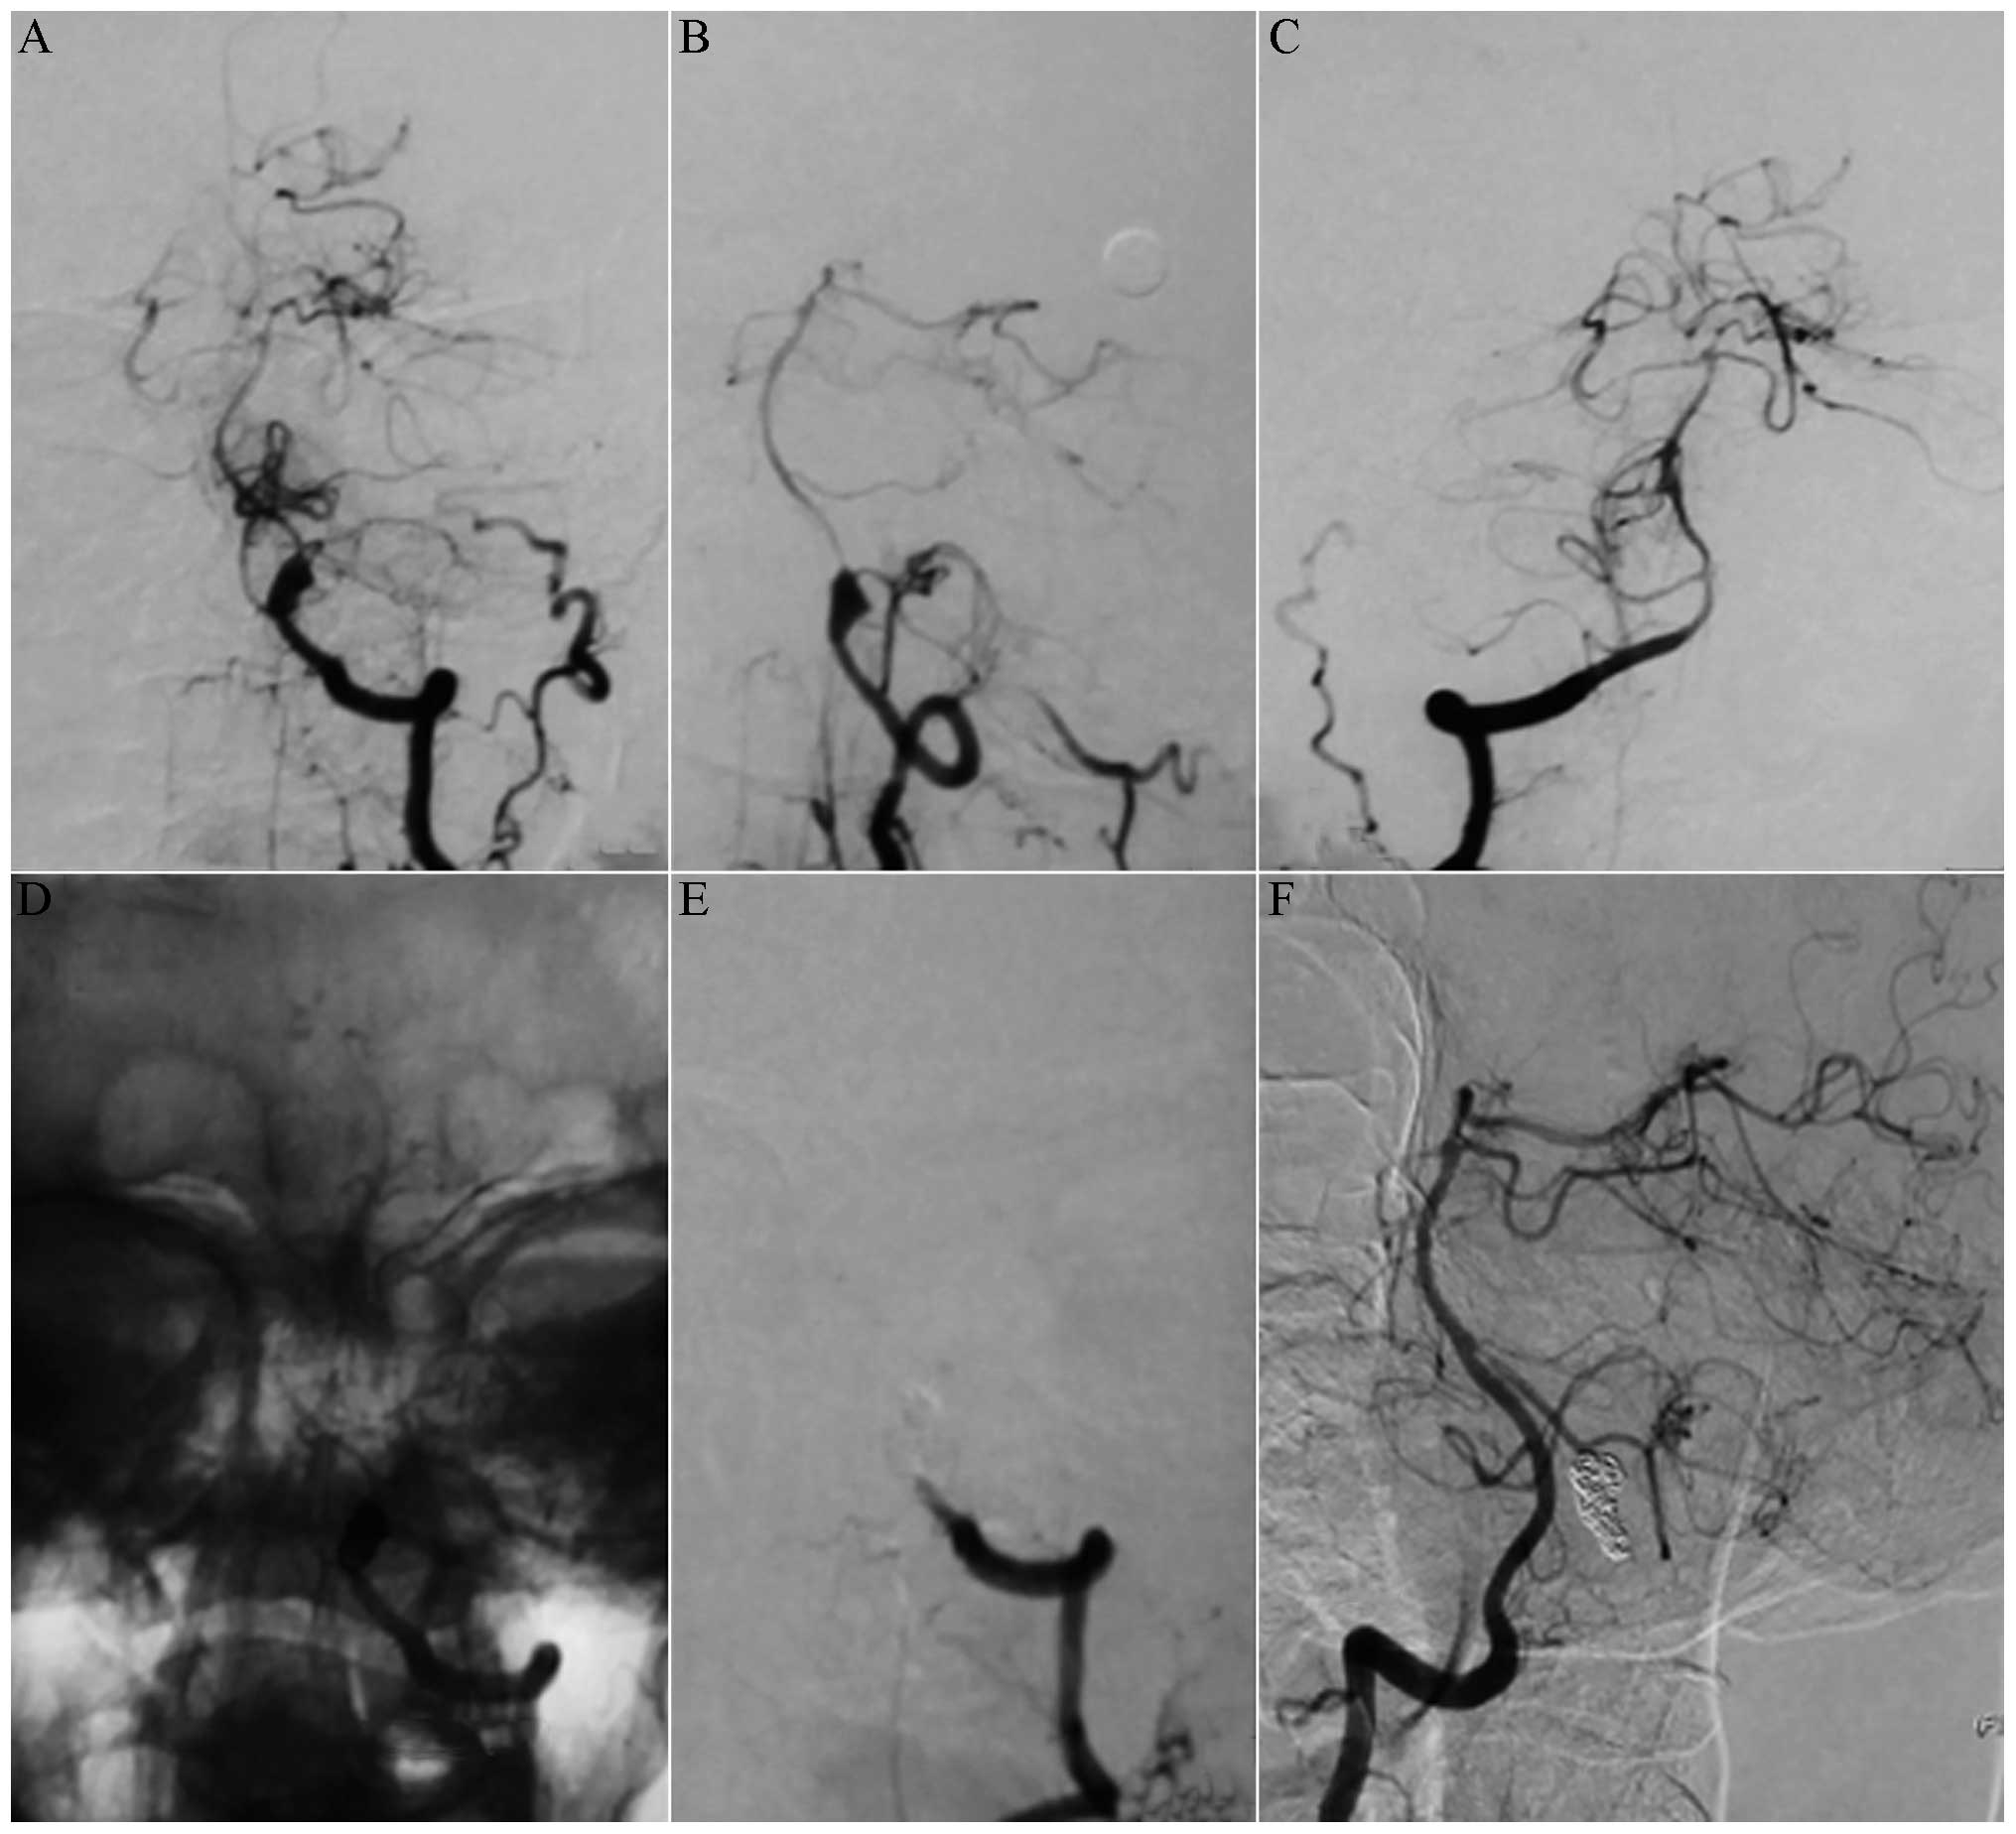

Among the 10 patients with type I aneurysms, four patients with type Ia received coiling with parent artery occlusion (Fig. 1), one patient with type Ia received stent-assisted coiling, three patients with type Ib received stent-assisted coiling (Fig. 2), one patient with type Ib received coiling only and one patient with type Ib was treated conservatively. Among the 13 patients with type II aneurysms, two patients with type IIa received coiling with parent artery occlusion (Fig. 3), five patients with type IIa received stent-assisted coiling (Fig. 4) and all six patients with type IIb received stent-assisted coiling. Among the eight patients with type III aneurysms, four patients with type IIIa received coiling with parent artery occlusion (Fig. 5), one patient with type IIIa received stent-assisted coiling (Fig. 6), two patients with type IIIb received stent-assisted coiling and one patient with type IIIb received coiling only.

Figure 1

(A) Digital subtraction angiography (DSA) and (B) 3D-DSA images showing a well-developed type Ia dissecting aneurysm of the left vertebral artery located distally to the posterior inferior cerebellar artery (PICA) and the contralateral vertebral artery. (C) DSA images of the right vertebral artery and (D) an amplified image of the left vertebral artery. The aneurysm was treated with coiling combined with left vertebral artery occlusion. The post-treatment angiograms show complete obliteration of the aneurysm, (E) occlusion of the distal part of the left vertebral artery and (F) a well-filled PICA.